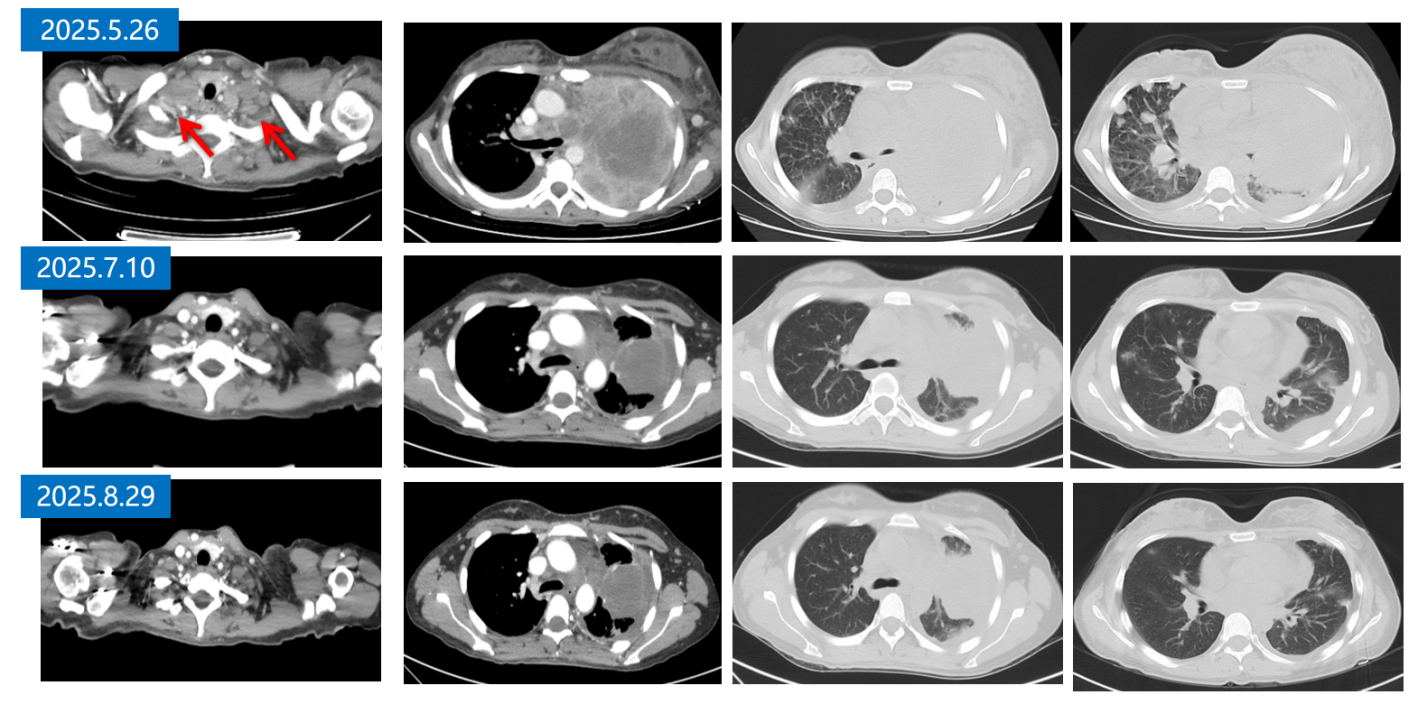

疗效评估:治疗仅3周后,患者病情迅速恶化。自觉胸闷加重,左乳及左侧肢体明显肿胀,胸部静脉怒张。2025年5月26日,胸部CT示左肺病灶及纵隔淋巴结较前明显增大,左乳皮下水肿明显,出现心包积液,2025年5月27日行心包穿刺引流黄色液体500ml。

11.png

一线治疗前后胸部CT(肺窗)

111png.png

一线治疗前后胸部CT(纵隔窗)

疗效评估:2025-7-10及2025-8-29复查胸部CT,显示左肺占位及肿大淋巴结缩小,疗效评估为部分缓解(PR)

33png.png

二线治疗前后胸部CT